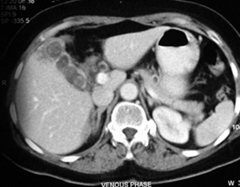

CT Scan Showing Cancer GallBladder

CT Scan Showing Cancer Gall Bladder